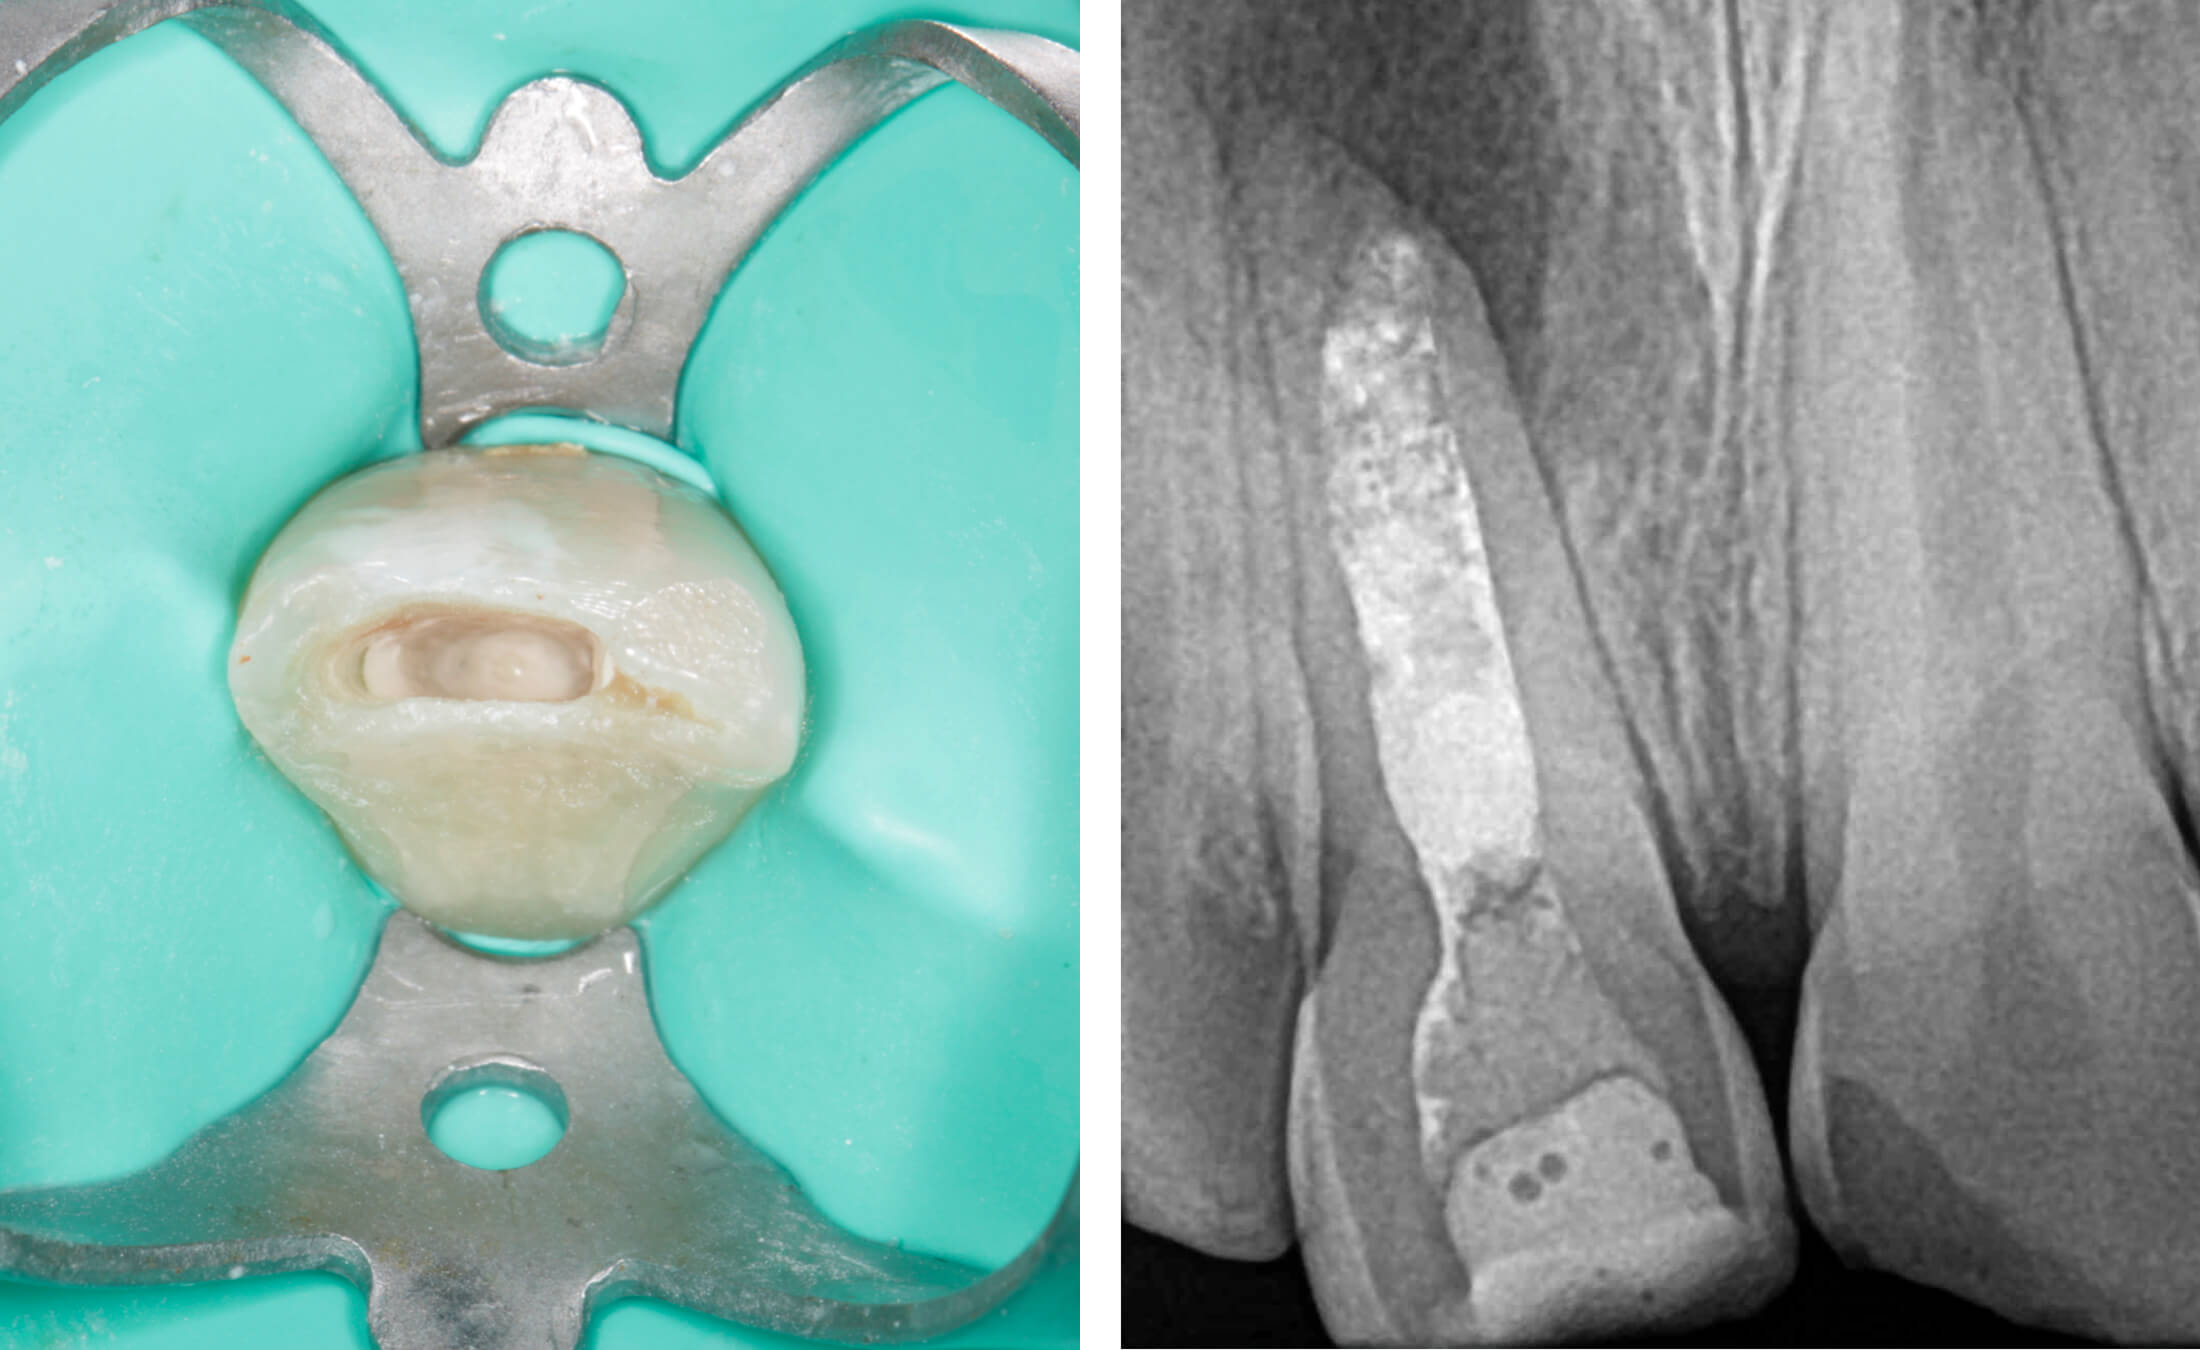

4. During the second appointment, the root canal treatment was completed. First, a 4-5 mm apical barrier was created using MTA (Mineral Trioxide Aggregate).

Following MTA setting, the remaining canal space was obturated with gutta-percha points using the cold lateral compaction technique, accompanied by an epoxy resin-based sealer (AH Plus). This approach ensures three-dimensional sealing of the root canal system. A control radiograph confirmed proper filling length with no material extrusion beyond the apex. (Image 7-10)